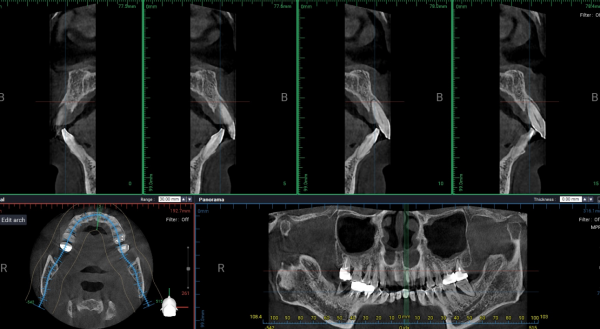

파노라마 및 CBCT 분석 결과,

* 전반적인 만성 치주염 소견

* 상·하악 치조골의 광범위한 흡수

* 특히 상악 전치부에서 수직·수평적 골 소실이 현저

* 치근 대비 잔존골 높이 및 폭 모두 제한적

즉, 환자가 느끼는 불편은 앞니였으나

실제 문제는 이미 치조골 단계에서 진행 중인 상태였다.